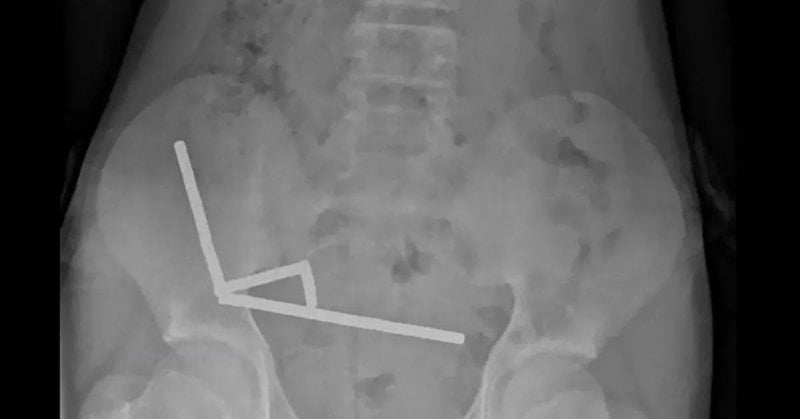

وكشفت الأشعة أنّ المغناطيسات تجمّعت داخل أمعاء المراهق في أربعة خطوط مستقيمة، حيث التصقت أجزاء مختلفة من الأمعاء ببعضها بفعل القوى المغناطيسية، ما أدّى إلى موت أنسجة في أجزاء من الأمعاء الدقيقة والغليظة.